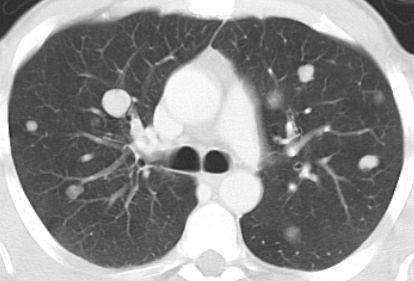

Lungenmetastasen nach NNR-Karzinom![]() | |||